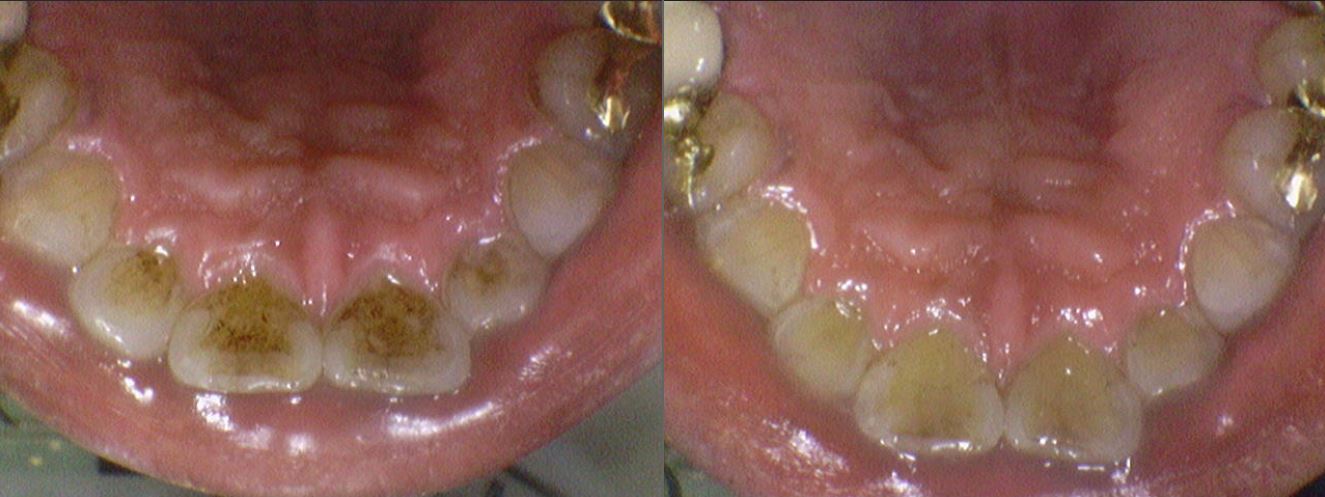

2. 내부 요인에 의한 착색

내부 착색은 치아 내부에서 발생하는 변색을 의미합니다.

- 항생제 사용: 어린 시절에 테트라사이클린과 같은 특정 항생제를 복용한 경우, 치아가 회색 또는 갈색으로 변색될 수 있습니다.

- 과도한 불소: 어린 시절에 불소를 과다하게 섭취하면 치아에 백색 반점이나 갈색 착색이 생길 수 있습니다.